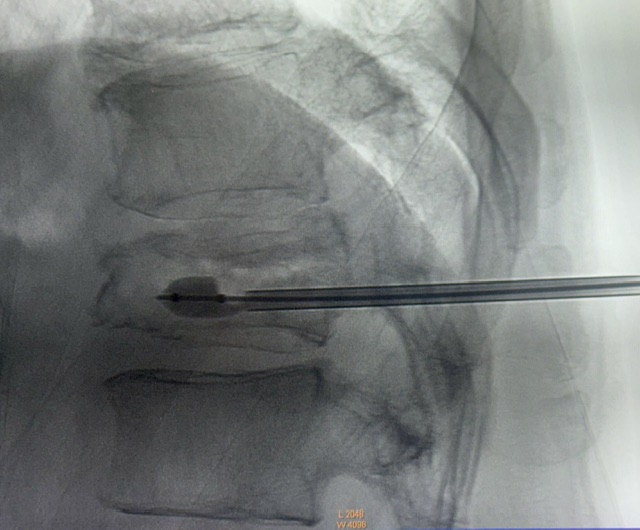

CAZ nr 91: Kifoplastie unipediculară cu balon pentru tasare vertebrală

Figura 3: Imagine statică din angiografie în plan sagital pentru poziționarea acului

Se practică kifoplastie unipediculara cu balon.